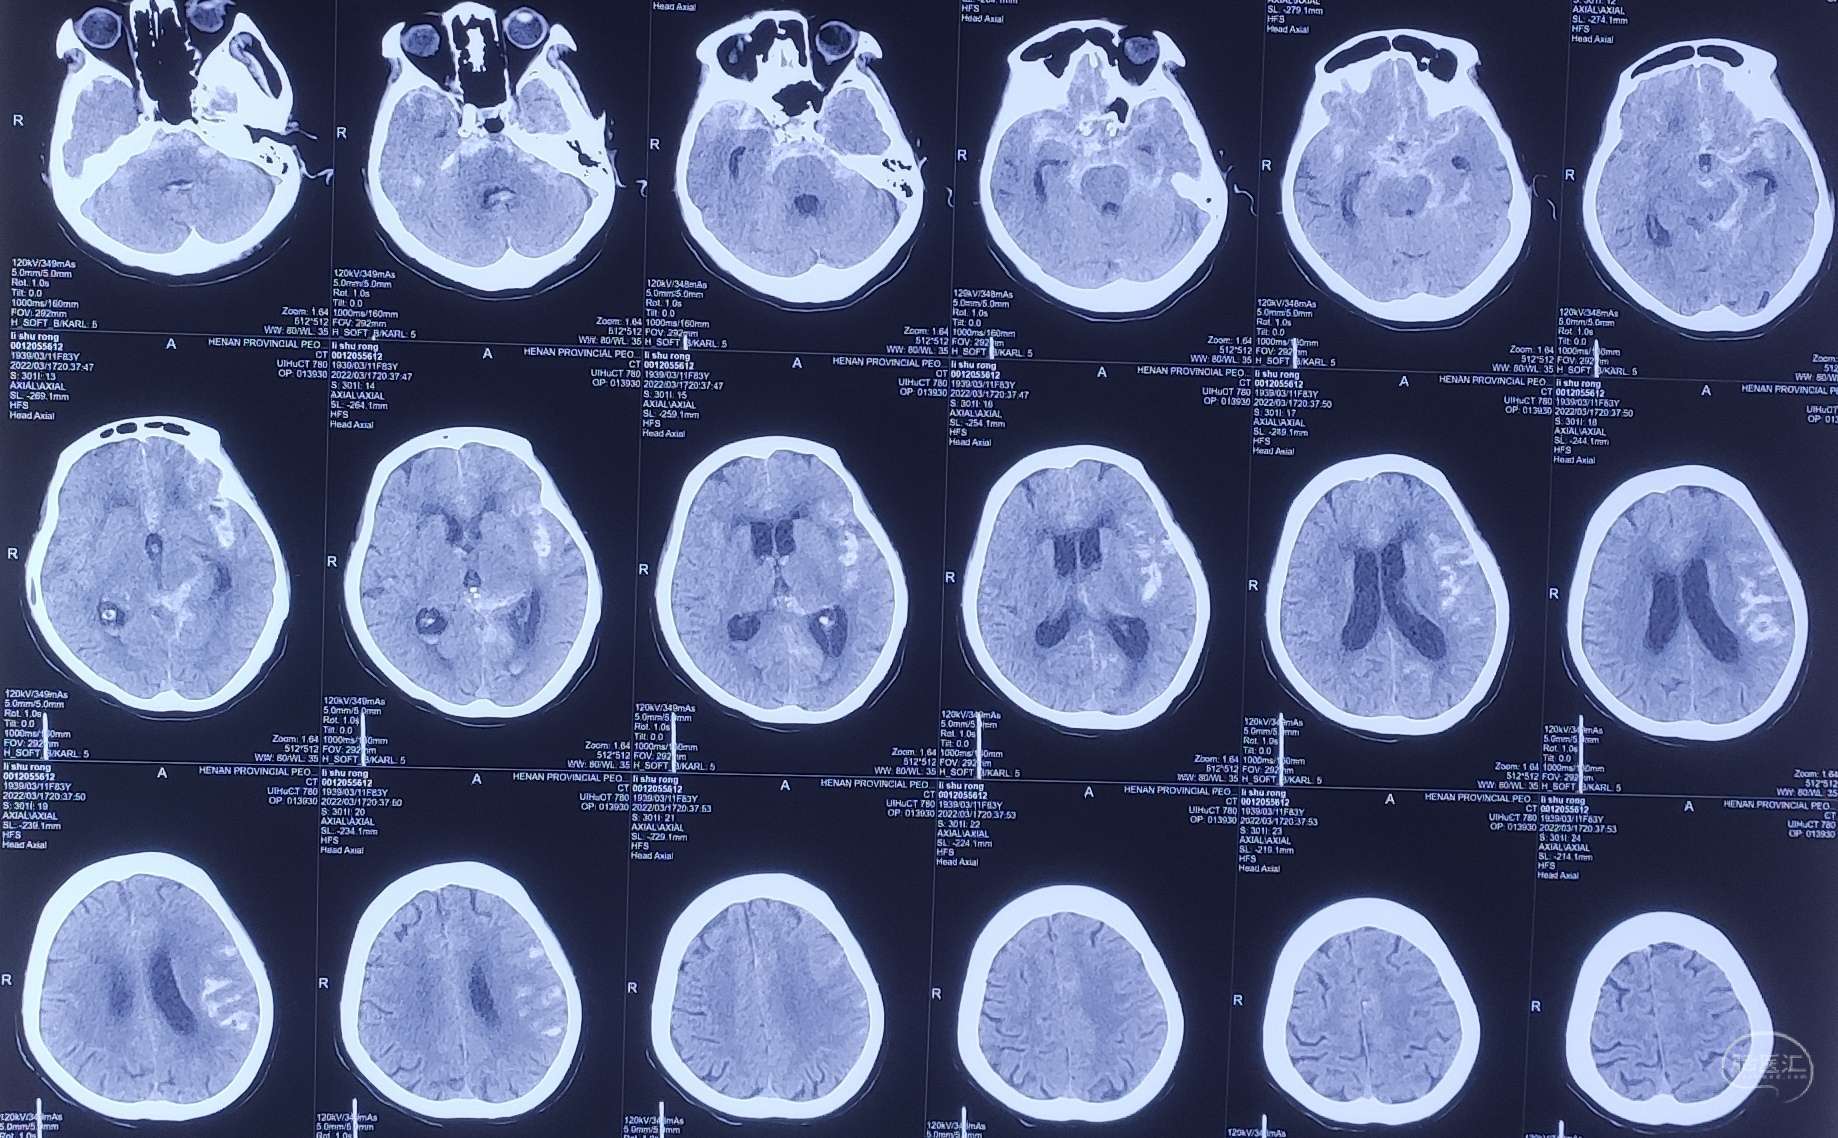

病例1 老年女性,蛛网膜下腔出血,SAH2级,诊断:左侧后交通动脉瘤。

头颅CT:蛛网膜下腔出血。